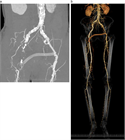

1. LEADは急性下肢虚血と慢性下肢虚血に大別される改訂JG)。

1. 慢性下肢虚血は無症候性と症候性に分けられ、症候性は間歇性跛行と包括的高度慢性下肢虚血(CLTI)に分けられるJG)。